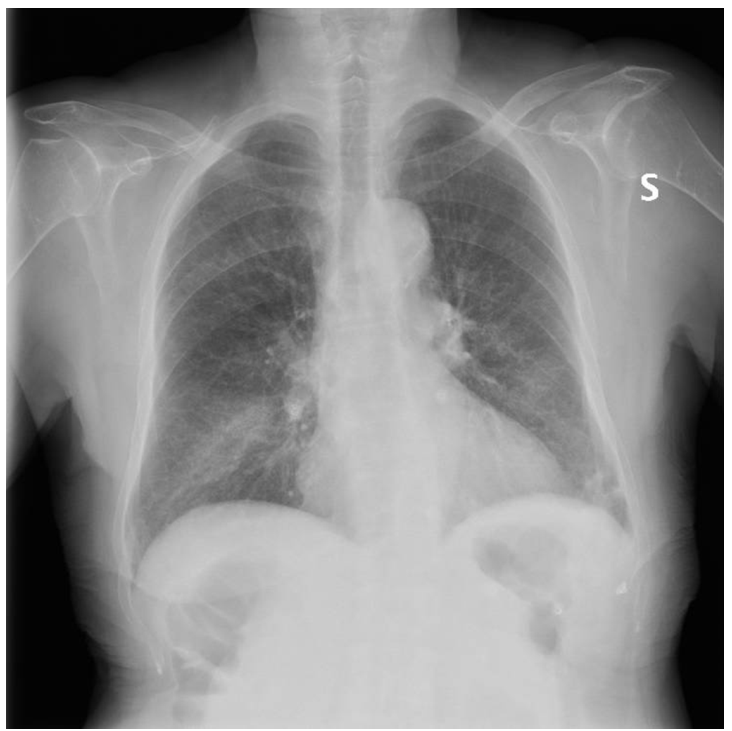

A chest X-ray is performed. The image shows interstitial thickening at the bibasal level, in the context of which a blurred thickening can be seen at the base of the right lung.

unnamed.png